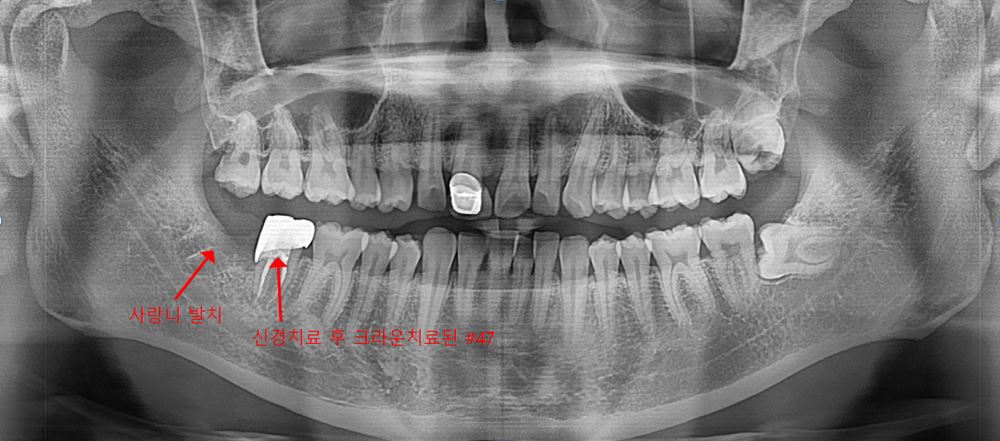

[치료 완료 후 파노라마]

매복 사랑니 발치 완료

신경치료 후 크라운치료까지 완료된 상태